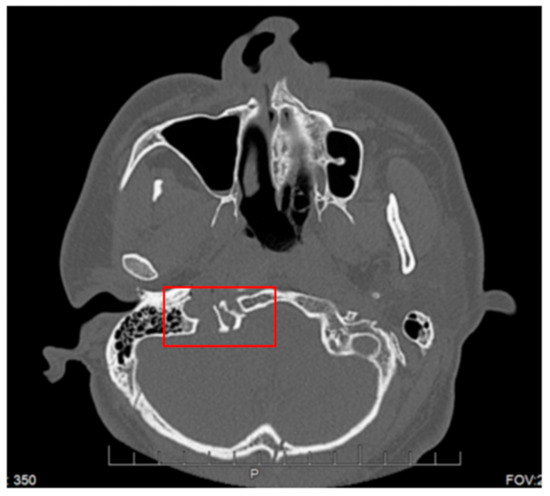

Collet–Sicard Syndrome has rarely been described as a consequence of blunt head trauma. Injuries to the jugular foramen and the hypoglossal canal are rare, as most blunt head traumas resulting in basilar skull fracture involve the condyles. In most cases, the condition is self-limiting, with patients regaining most to all of their neurological functions within 6 months. Several theories have been proposed for the pathophysiology of this syndrome. Displaced bony fragments that could compress the nerves in the context of fracture extension to the posterior jugular foramen or to the hypoglossal canal has been one theory to explain the neurological manifestations seen with CSS [6]. Bridgman et al. suggested that the cranial nerves were damaged by traction injuries [7]. Orbay et al. reported a case in which hypoglossal nerve palsy occurred 3 months after a head injury and suggested that a scarring process and the formation of a callus at the level of the hypoglossal canal could progressively compress the main hypoglossal nerve [8]. One of the more recent theories is that soft tissue edema, as a consequence of the local injury, compresses the cranial nerves (9, 10, 11 and 12) and leads to their deficits. With time, as the edema resolves, the neurological deficits also resolve [9]. The initial fracture, as can be seen by Figure 1, demonstrates a fracture on the border between the jugular foramen and the hypoglossal canal. CT of the Temporal bone better demonstrates the fracture location (See Figure 2). A subsequent MRI of the brain also demonstrates an area of hypo-attenuation, consistent with edema at the location of the jugular foramen and the hypoglossal canal (Figure 3). Treatment for CSS with blunt head trauma remains conservative, as other causes, such as a tumor or vascular impingement, require treatment of the underlying cause. As the edema resolves, so do neurological deficits. Some authors have advocated the anecdotal use of steroids to reduce the edema; however, as this case is very rare, large multi-institutional trials are warranted to better elucidate the role of steroids with Collet–Sicard syndrome. Of important note is to readily identify this condition and provide nutritional support with feeding tubes, as the recovery time is generally 3–6 months. In conclusion, injuries with focal neurological deficits which were not apparent on initial imaging should be reviewed by relevant experts with concomitant knowledge of the patient’s history and experience in neuroimaging.

Figure 1. CT maxillofacial. Red box indicates junction of Jugular foramen and Hypoglossal Canal.